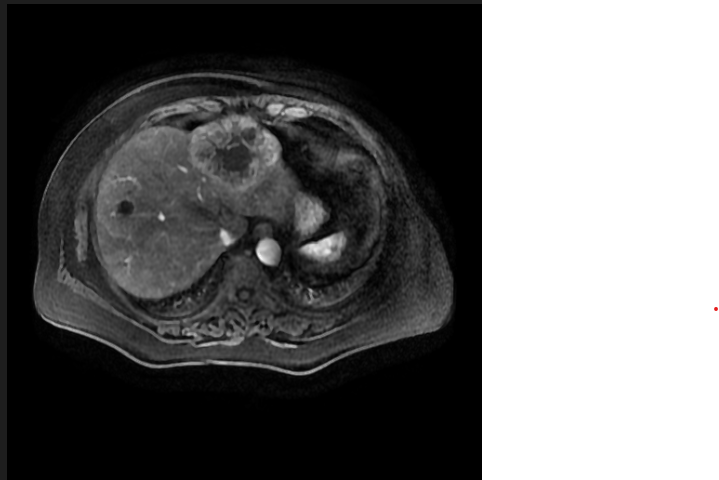

而原始图像是: